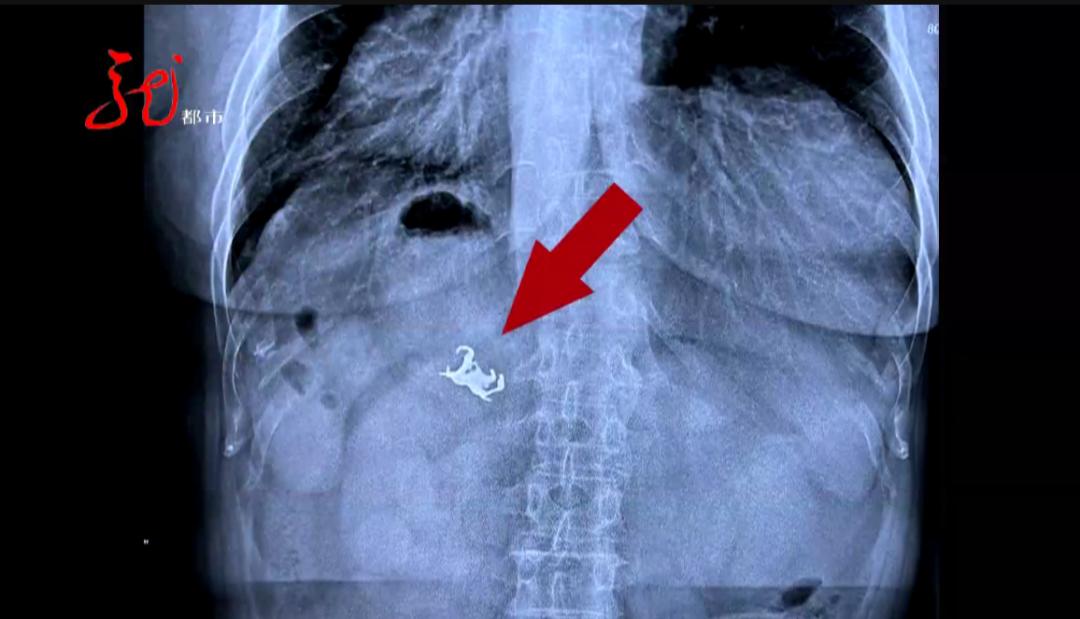

远看像个小蜘蛛

近看又像是个开瓶器

仔细再看看

这是一副假牙!

大庆市龙南医院消化内科负责人 副主任医师 黄波 是五个爪的,当时就很确认了,是假牙掉到胃里了。

大庆市龙南医院收治的这名57岁女性患者,自述肚子疼得难受,竟然是 吃饭时假牙挂钩松动,直接和饭菜一起进了肚。